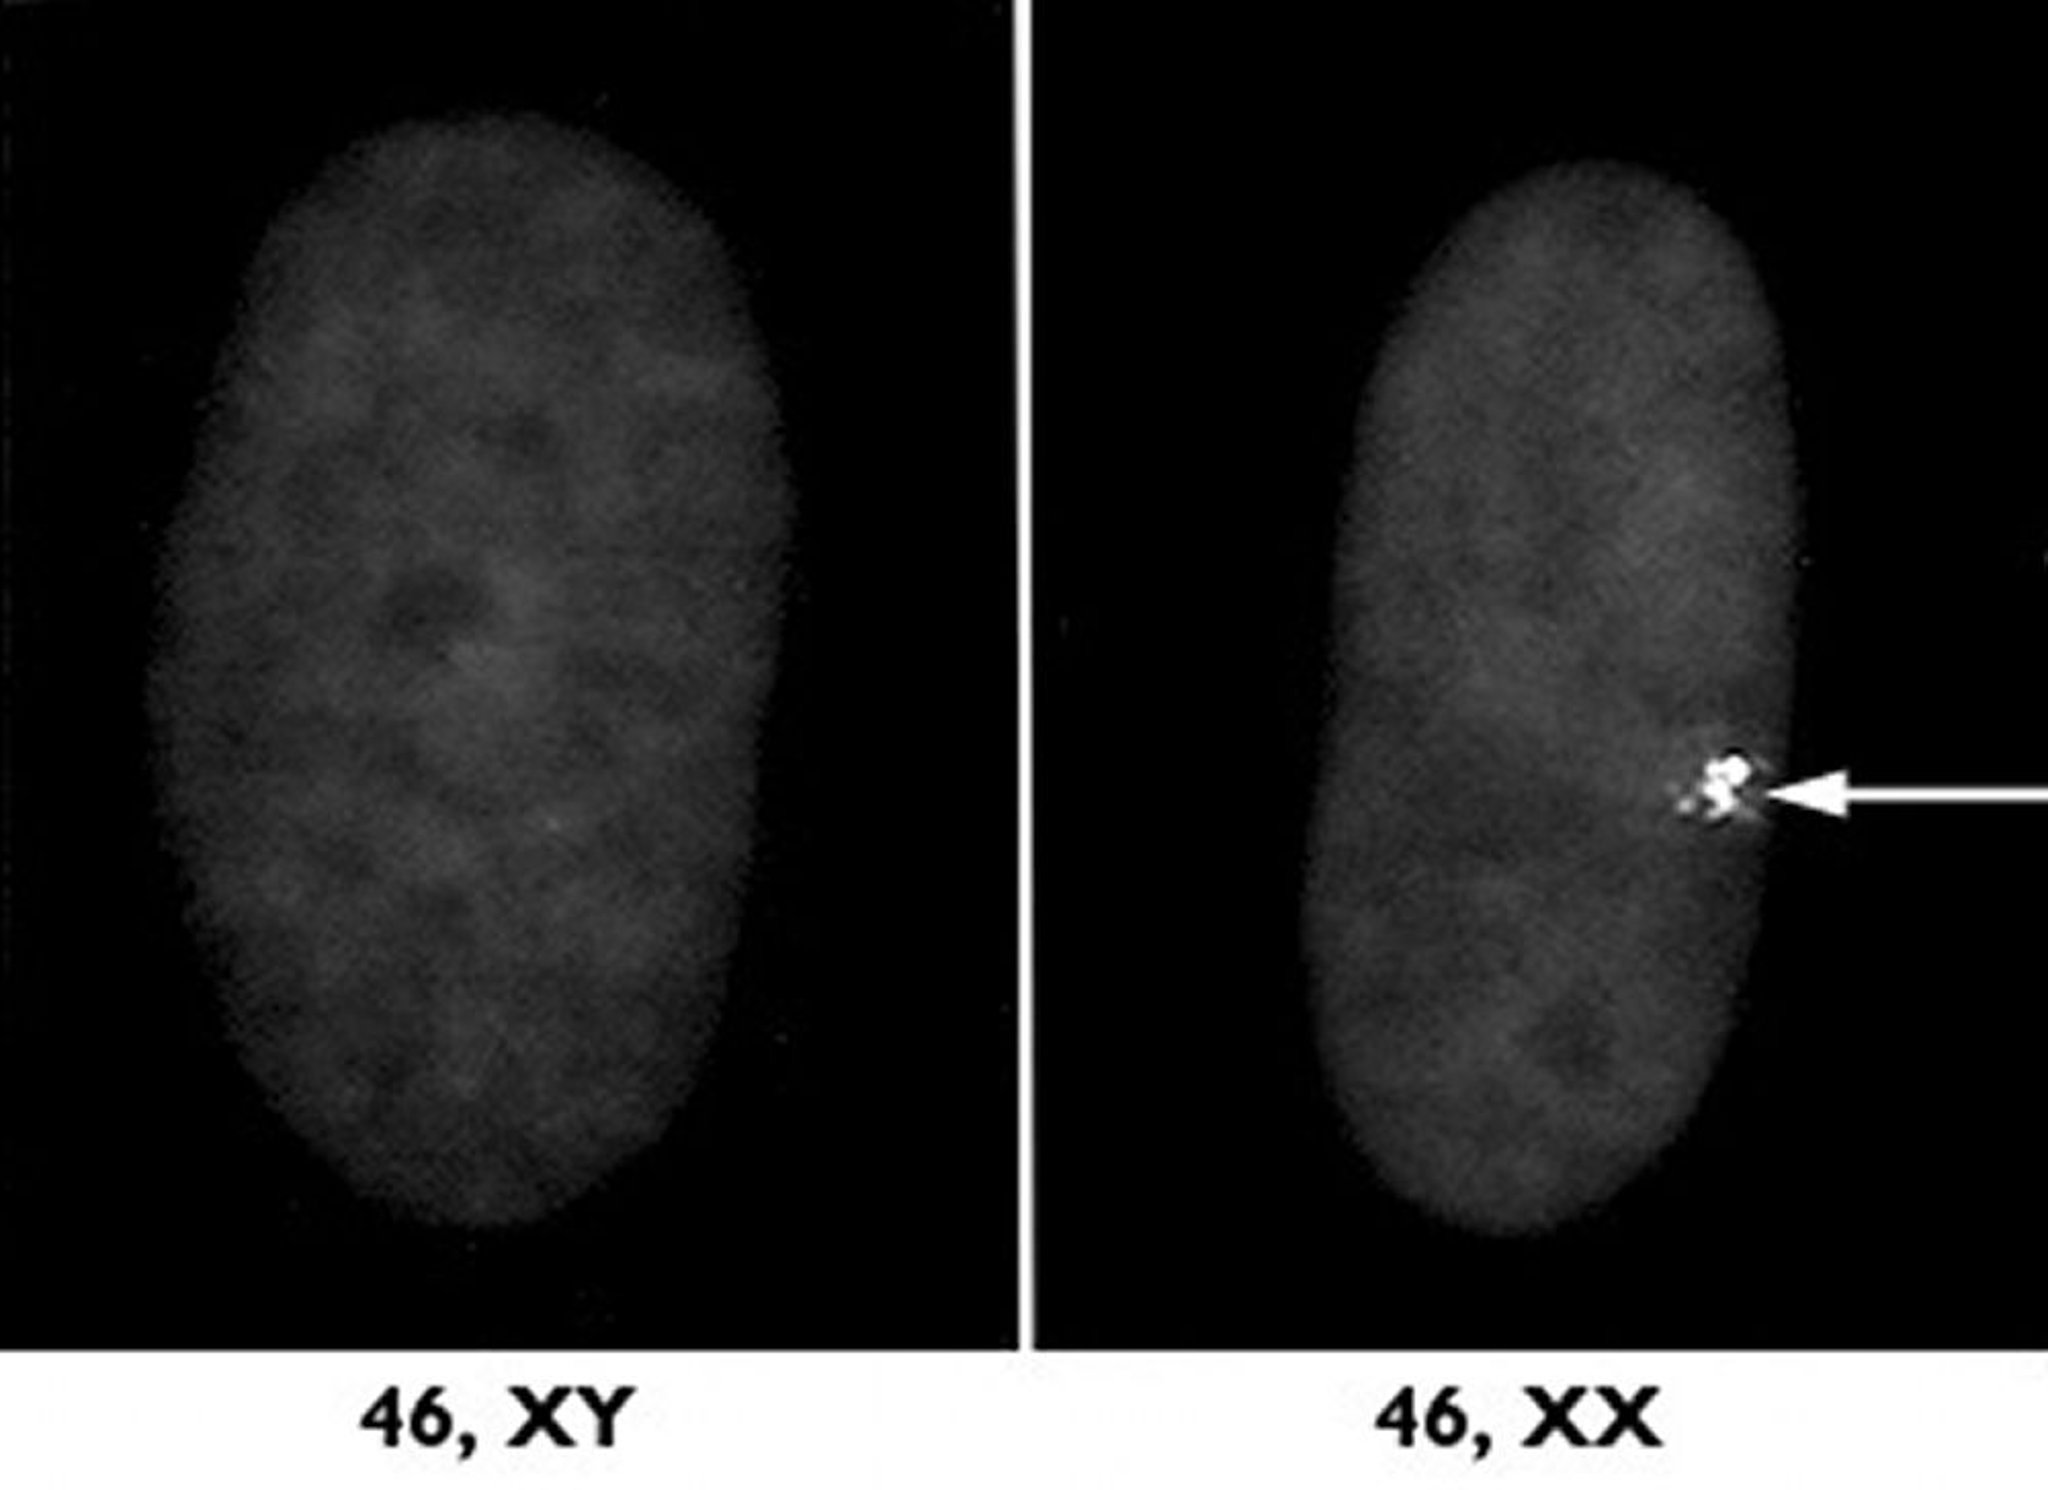

तेईसवीं जोड़ी सेक्स क्रोमोसोम (X और Y) है।

सेक्स क्रोमोसोम

सेक्स क्रोमोसोम का जोड़ा निर्धारित करता है कि भ्रूण लड़का होगा या लड़की। नर में एक X और एक Y क्रोमोसोम होता है। नर का X क्रोमोसोम उसकी मां से आता है और Y क्रोमोसोम पिता से आता है। मादाओं में दो X क्रोमोसोम होते हैं, जिनमें से एक मां से और एक पिता से आता है। कुछ तरीकों में, सेक्स हार्मोन नॉनसेक्स हार्मोन की तुलना में अलग तरह से कार्य करते हैं।

छोटे Y क्रोमोसोम में वो जीन जो नर लिंग का निर्धारण करते हैं और साथ ही कुछ अन्य जीन होते हैं। X क्रोमोसोम में Y क्रोमोसोम की अपेक्षा कहीं अधिक जीन होते हैं, जिनमें से बहुत से जीन के, लिंग निर्धारण के अलावा भी कार्य होते हैं और Y क्रोमोसोम पर इसका कोई प्रतिरूप नहीं होता। नर में, चूंकि कोई दूसरा X क्रोमोसोम नहीं होता, इसलिए X क्रोमोसोम पर ये अतिरिक्त जीन युग्मित नहीं होते और वस्तुतः उनमें से सभी अभिव्यक्त होते हैं। X क्रोमोसोम पर उपस्थित जीन को सेक्स-लिंक्ड या X-लिंक्ड जीन कहा जाता है।

सामान्यतः, नॉनसेक्स क्रोमोसोम में, क्रोमोसोम के दोनों जोड़ों पर उपस्थित जीन पूर्ण रूप से अभिव्यक्त होने में सक्षम होते हैं। हालांकि, मादाओं में, दोनों X क्रोमोसोम में से एक पर उपस्थित अधिकांश जीन X निष्क्रियण नामक प्रक्रिया के माध्यम से बंद हो जाते हैं (अंडाशयों में मौजूद अंडों में छोड़कर)। X निष्क्रियण प्रायः भ्रूण के जीवन के आंरभिक समय में घटित होता है। कुछ कोशिकाओं में, पिता से मिला X क्रोमोसोम निष्क्रिय हो जाता है, और अन्य कोशिकाओं में, माता से मिला X क्रोमोसोम निष्क्रिय हो जाता है। इसलिए, एक सेल में व्यक्ति की माँ से मिला जीन हो सकता है और दूसरे सेल में व्यक्ति के पिता से मिला जीन हो सकता है। X निष्क्रियण के कारण, एक X क्रोमोसोम की अनुपस्थिति के परिणामस्वरूप आमतौर पर अपेक्षाकृत मामूली असामान्यताएं (जैसे टर्नर सिंड्रोम) होती हैं। इसी प्रकार, एक X क्रोमोसोम के गायब होने से किसी नॉनसेक्स क्रोमोसोम के गायब होने की तुलना में बहुत कम हानि पहुंचती है (सेक्स क्रोमोसोम संबंधी असामान्यताओं का संक्षिप्त विवरण देखें)।